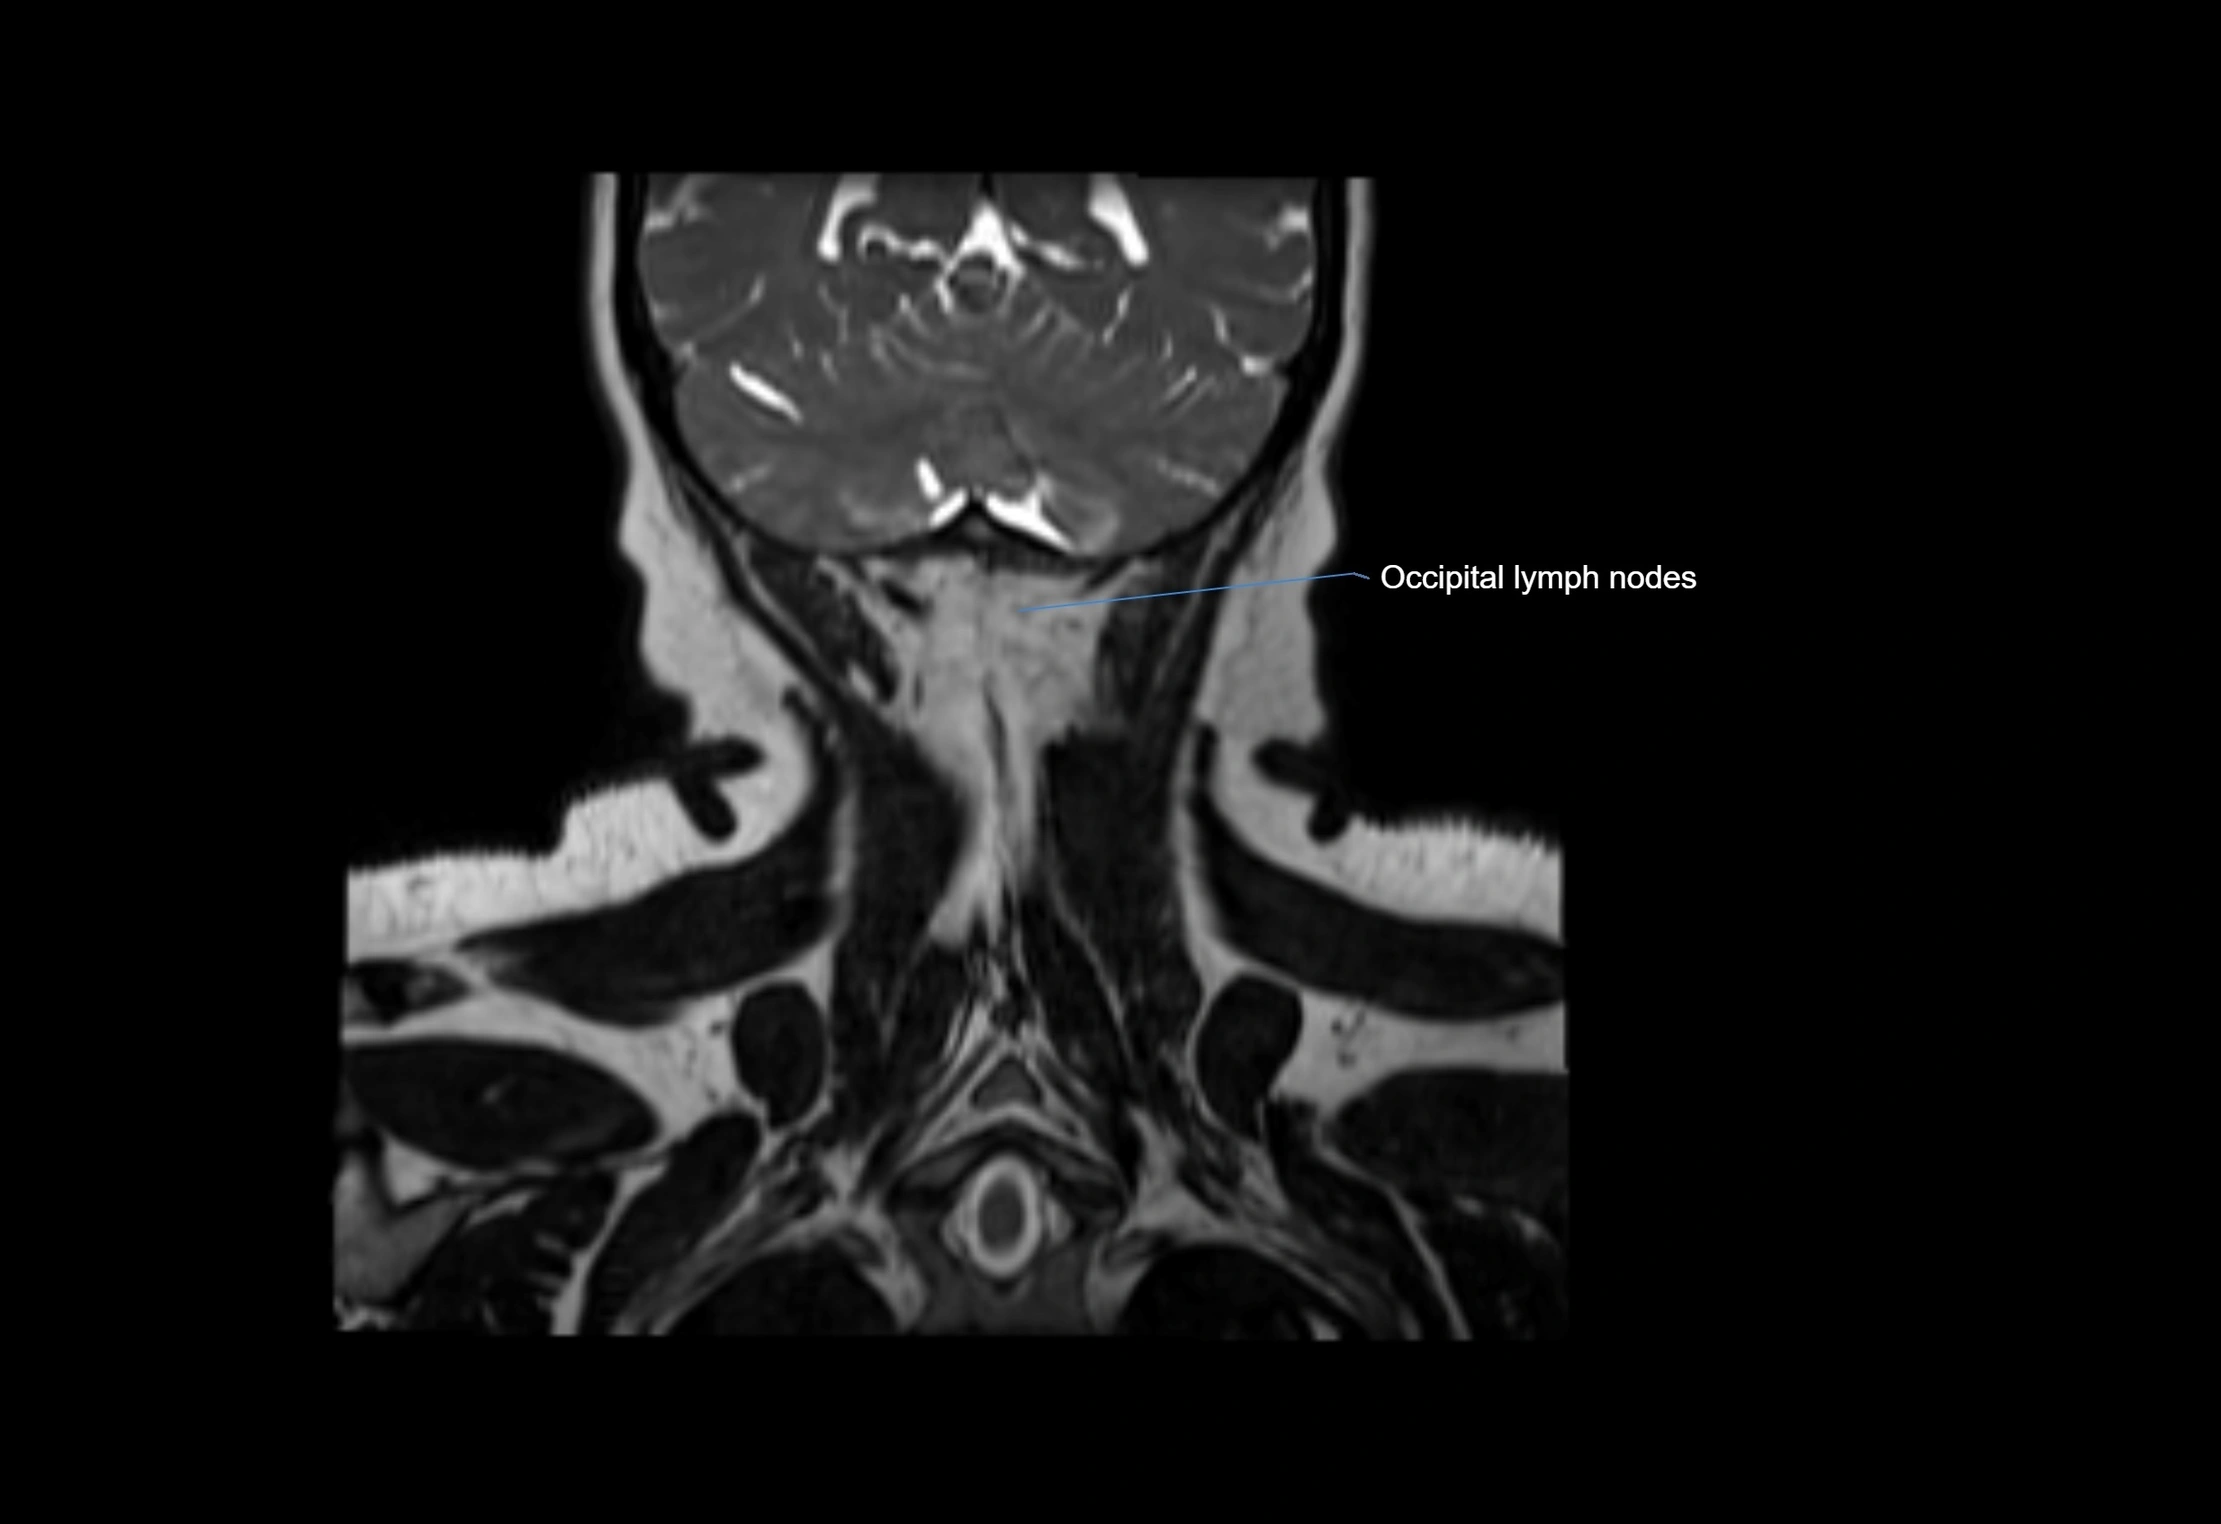

Location

• Found along primary lymph node chains, including preauricular, submandibular, parotid, and occipital regions

• Embedded in subcutaneous fat or superficial fascia, often lateral or posterior to primary nodes

• Variable in number; may occur unilaterally or bilaterally, depending on individual anatomy

MRI images

image